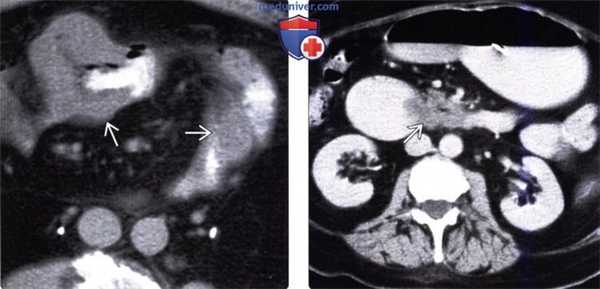

(Слева) На аксиальной КТ с контрастом у мужчины 69 лет, у которого ранее была обнаружена распространенная меланома, визуализируются типичные диссеминированные метастазы меланомы, вт. ч. в стенке желудка и лимфоузлах. Метастазы в стенке желудка могут изъязвляться, принимая вид «мишени» либо «бычьего глаза».

(Справа) На КТ у этого же пациента визуализируются распространенные метастазы, в т. ч. в тонкой кишке, лимфоузлах и сальнике в виде узлов и диффузного поражения этих органов. Определяется также обструкция правого мочеточника из-за его вторичного поражения.

о Метастазы злокачественной меланомы:

- Дискретные узлы в стенке кишки в виде «бычьего глаза» или «мишени»:

Накапливают контраст, выбухают в просвет, вызывают утолщение стенки тонкой кишки на ограниченном участке

- Объемные образования в брыжейке тонкой кишки, органах брюшной полости и т. д.

- Подслизистые образования с бугристыми краями или гигантские кавитирующие образования (аневризматическая дилатация)

- Большое объемное интрамуральное образование, не обусловливающее обструкцию, скорее всего, является меланомой или лимфомой, но не карциномой

- Может становиться причиной развития инвагинации

(Слева) На аксиальной КТ с контрастным усилением у пациента с меланомой, у которого наблюдалось снижение веса и появилась диарея, визуализируются большие, изъязвленные образования в сочетании с аневризматическим расширением просвета тонкой кишки, в то же время, не определяется признаков тонкокишечной обструкции.

(Справа) На аксиальной КТ с контрастным усилением, выполненной женщине, у которой ранее был обнаружен рак молочной железы, определяется расширение желудка и двенадцатиперстной кишки с резким сужением просвета ее третьей части, обусловленное образованием в стенке. Во время операции был подтвержден метастаз рака молочной железы.